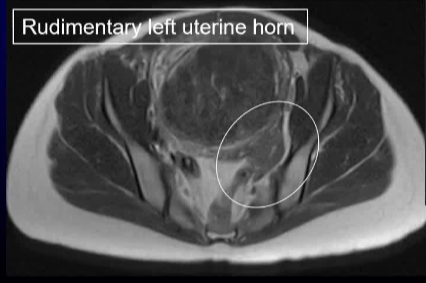

47 岁的 G1P1 女性因持续两年的月经过多症状前来就诊。 症状还包括盆腔痉挛性疼痛、尿频和背痛。妇科病史显示存在一种已知的苗勒管异常(MDA)。按照方案要求进行了盆腔磁共振成像(MR)检查,以评估子宫肌瘤栓塞术(UFE)的情况。检查结果显示为单角子宫,其主导的右侧子宫角存在强化的全层和黏膜下肌瘤,左侧则有一个相通的原始子宫角。 MR 还显示右侧有一个孤立的肾脏,右侧子宫动脉占主导地位,而左侧的子宫动脉和卵巢动脉均无法辨认。 子宫肌瘤被认为是导致月经过多和下腹肿块症状的原因。